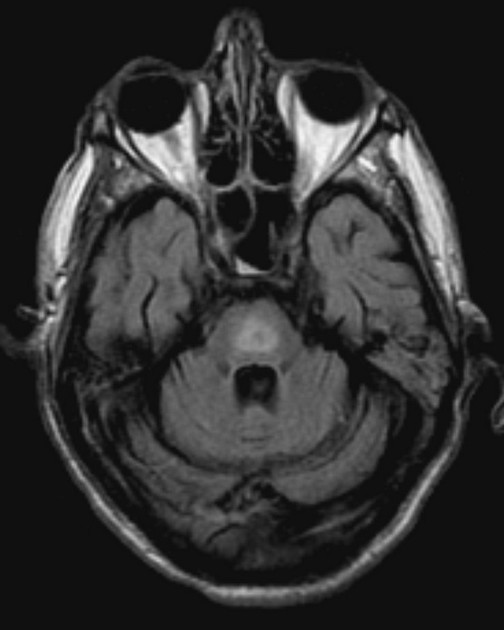

hot cross bun sign

hyperintensities of cerebellar peduncles